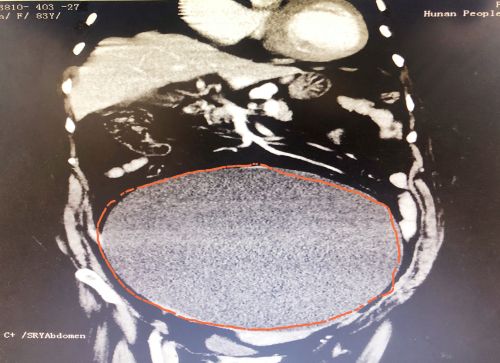

ct显示,肿瘤几乎占据老人整个盆腔和腹腔。

2021年1029日,彭娭毑住进湖南省人民医院妇科病房。完善相关检查发现,巨大的肿瘤几乎占据她整个盆腔和腹腔,并且压迫肠道和膀胱,这也是老人尿频的原因。与此同时,术前血液检查发现了异常——全系细胞减少,进一步骨髓穿刺结果为:可疑B细胞淋巴瘤骨髓浸润。

经过充分讨论并做好充足的术前准备后,1112日,妇科黄薇主任团队在麻醉科、手术室的配合下,秉持无瘤操作原则,为老人施行单孔腹腔镜手术。在她肚脐上打一个小孔,缓慢引流出约4000毫升清亮的囊液。术中发现,左侧巨大的卵巢肿瘤与肠管致密大片粘连;精细分离后,顺利切除缩小的卵巢肿瘤和双侧附件,快速病检证实为“双侧卵巢浆液性囊腺瘤”。